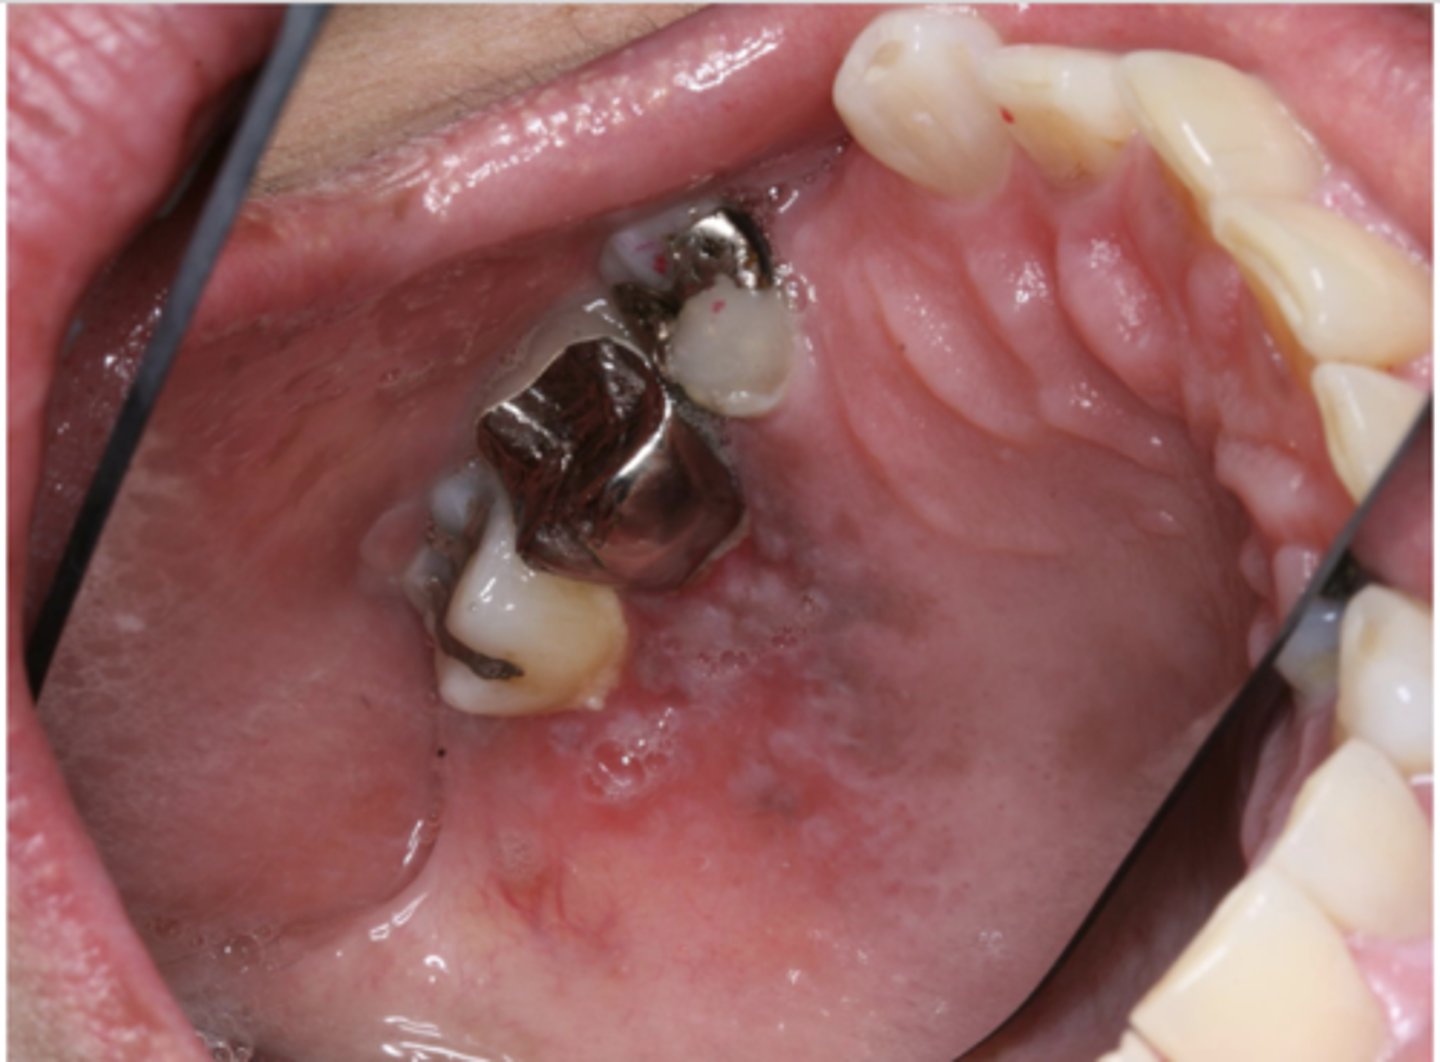

What type of pigmented lesion?

amalgam tattoo

These are clinical features of what?

- Asymptomatic, localized

- Blue-gray macule

- Localized around areas with amalgam restorations

amalgam tattoos

What is the most common location of amalgam tattoos?

gingiva/alveolar ridge mucosa (50%, then buccal mucosa, then floor of mouth)